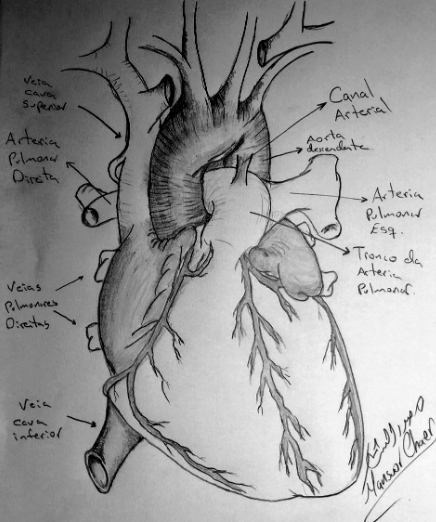

Figura 1. Desenho anatômico do canal arterial. Fonte: cortesia do Dr. Mansuor Chaer Alameddin para esta publicação. O canal arterial…